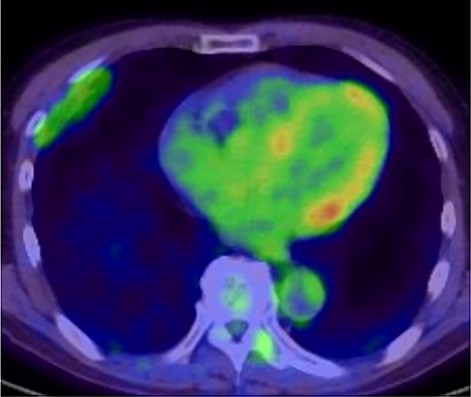

A 72-year-old man with a history of hypertension and left renal cancer (Stage I) was referred to us with a mass in the right chest wall on post-operative follow-up chest computed tomography (CT) for renal cancer. He had a smoking history of 20 pack-years and had no exposure to environmental fumes or dust. Physical examination results were unremarkable. The laboratory findings were within normal limits. Pulmonary function tests and cardiovascular examinations revealed normal results. Chest CT revealed mixed density mass (8.0 × 5.0 × 3.0 cm) located in front of thoracic wall in the third to sixth right intercostal space. The tumor can be revealed as thoracic wall fat (7.8 × 4.8 × 1.2 cm) on CT 1 year before (not considered as abnormal), and it was progressively increased in size and the density changed (Fig. 1A and B). Magnetic resonance imaging (MRI) showed a fatty mass of heterogenic density. T2 high foci (Fig. 2A) and irregular marginal enhancement of the tumor were observed (Fig. 2B). Maximal standard uptake value (SUVmax) of 18F-fluorodeoxyglucose positron emission tomography (FDG-PET) was 3.78 (Fig. 3). Based on these radiological image findings, we scheduled surgery with suspicion of liposarcoma. During the surgery, the patient was placed in the lateral decubitus position. We made 1.5-cm incision in the sixth intercostal space along the posterior axial line for thoracoscopy. We found dense adhesions between the chest wall tumor, lung (front part of all three lobes of the right lung) and diaphragm. We made a 30-cm incision in the fourth intercostal space and resected the tumor along with lung (wedge resection of the front part of all three lobes of the right lung), diaphragm and third to sixth ribs and intercostal muscle. The chest wall defect was 25 × 15 cm and the diaphragm defect was 8 × 5 cm. For reconstruction, the mesh was placed and sutured to the diaphragm and the chest wall. Pathological examination revealed the well-circumscribed tumor with fibrous adhesion between the ribs, lung and diaphragm (Fig. 4A). Microscopically, the tumor consisted of mature fat tissue. There were fat necrosis inflammatory changes in the marginal area of the tumor with foamy macrophages and multinucleated giant cells (Fig. 4B and C). Fluorescence in situ hybridization examination for murine double-minute 2 was negative. Based on these findings, a chest wall lipoma was diagnosed. The post-operative course was uneventful. The patient was followed up for 24 months without evidence of recurrence.

18F-FDG-PET uptake by the tumor; maximum standard uptake value was 3.78.

In the present case, tumor enlargement with heterogenic change of the density, thickened septa >2 mm, prominent foci of high T2 signal and prominent areas of enhancement on MRI were seen on preoperative CT and MRI. In addition, the SUVmax of FDG-PET was higher than that of simple lipoma (SUVmax = 3.78). These findings led to a misdiagnosis for liposarcoma. Furthermore, intraoperative findings of dense adhesion between the tumor and surrounding structures strengthen our suspicion of liposarcoma. We could not find another case of intrathoracic lipoma of the chest wall with density change on radiological image and dense adhesion between the surrounding structures.

Pathological findings in this case showed fat necrosis and inflammatory changes in the marginal area of the tumor, with foamy macrophages, and multinucleated giant cells. These changes may cause the malignant featured images, such as heterogenic density, enhancement on MRI and high SUVmax of FDG-PET. In addition, these changes may cause dense adhesion. Several lipomas with fat necrosis has been reported [8], but none of them have intrathoracic origin. In addition, no other cases with conspicuous radiological image change have been reported as in our case.